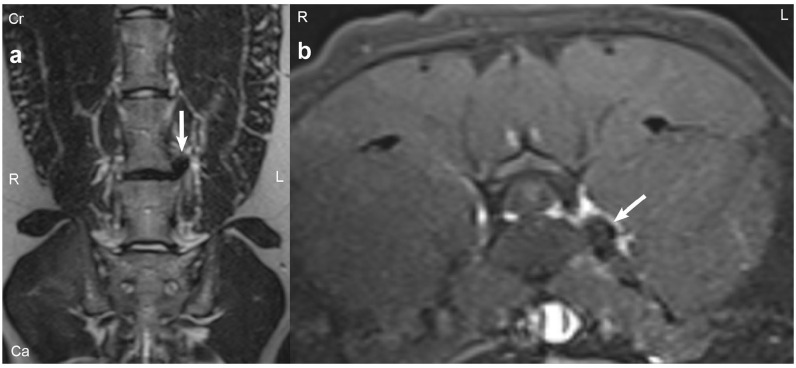

Case summary: A 9-year-old male castrated domestic shorthair cat was presented with a 2-week history of acute, progressive left pelvic limb lameness. Gait evaluation revealed a grade 3/5 left pelvic limb lameness with no apparent orthopedic cause for the lameness based on orthopedic examination or radiographs. The neurological examination was otherwise normal. MRI revealed a left-sided L6-7 far lateral intervertebral disc extrusion with possible secondary neuritis of the L6 spinal nerve. A left-sided L6-7 foraminotomy was performed to remove the extruded disc material and provide additional space for the significantly enlarged nerve root. An L6-7 fenestration was also performed. The patient made an excellent recovery with near-complete resolution of lameness at 26 days postoperatively.